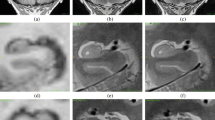

The hippocampus has a critical role in many common disease processes. Currently, routine 3 Tesla structural MRI is a mainstay of clinical diagnosis. The goal of our study is to evaluate the normal variability in size and/or conspicuity of the hippocampal subcomponents in routine clinical 3 Tesla high-resolution T2-weighted images to provide a basis for better defining pathological derangements. Additionally, we utilize diffusion data acquired from a 17.6 Tesla MRI of the hippocampus as a benchmark to better illustrate these subcomponents.

The hippocampus was retrospectively assessed on 104 clinically normal patients undergoing coronal T2-weighted imaging. The conspicuity of the majority of hippocampal subcomponents was assessed in each portion of the hippocampus. Additionally, easily applicable cross-sectional measurements and signal intensities were obtained to evaluate the range of normal, as well as inter- and intra-subject variability.

The normal range of cross-sectional measurements of the hippocampal subcomponents was calculated. There was minimal side-to-side variability in cross-sectional measurements of hippocampal subcomponents (< 5%) with the exception of the subiculum (R>L by 8.3%) and the CA4/DG (R>L by 5.8%). The internal architecture showed high variability in visibility of subcomponents between different segments of the hippocampus.